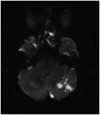

In this review article, we summarized the current advances in rescue management for reperfusion therapy of acute ischemic stroke from large vessel occlusion due to underlying intracranial atherosclerotic stenosis (ICAS). It is estimated that 24-47% of patients with acute vertebrobasilar artery occlusion have underlying ICAS and superimposed in situ thrombosis. These patients have been found to have longer procedure times, lower recanalization rates, higher rates of reocclusion and lower rates of favorable outcomes than patients with embolic occlusion. Here, we discuss the most recent literature regarding the use of glycoprotein IIb/IIIa inhibitors, angioplasty alone, or angioplasty with stenting for rescue therapy in the setting of failed recanalization or instant/imminent reocclusion during thrombectomy. We also present a case of rescue therapy post intravenous tPA and thrombectomy with intra-arterial tirofiban and balloon angioplasty followed by oral dual antiplatelet therapy in a patient with dominant vertebral artery occlusion due to ICAS. Based on the available literature data, we conclude that glycoprotein IIb/IIIa is a reasonably safe and effective rescue therapy for patients who have had a failed thrombectomy or have residual severe intracranial stenosis. Balloon angioplasty and/or stenting may be helpful as a rescue treatment for patients who have had a failed thrombectomy or are at risk of reocclusion. The effectiveness of immediate stenting for residual stenosis after successful thrombectomy is still uncertain. Rescue therapy does not appear to increase the risk of sICH. Randomized controlled trials are warranted to prove the efficacy of rescue therapy.